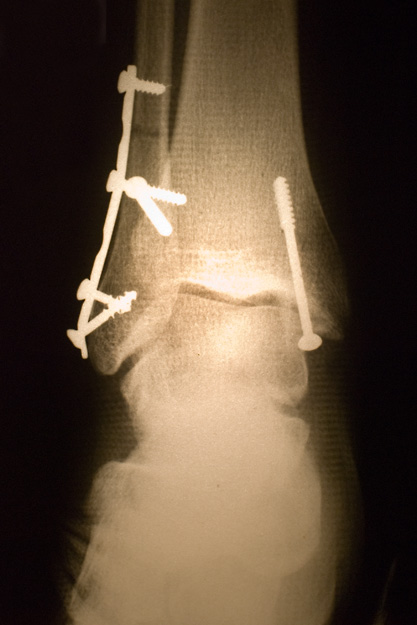

My housemate, Olivier, had a motorcycle accident and badly broke his ankle. Voila! The handiwork of the French Hospital in Hanoi.